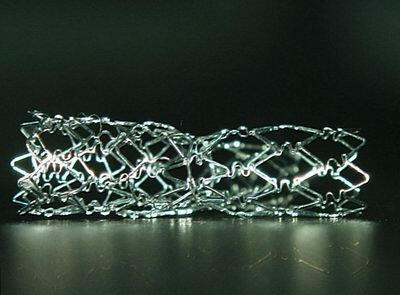

先日、CypherのベースになっているVelocityを使ってYステントの

実験をしてみました。ガイダント社で作成されたポリビニールアル

コール(PVA)製の冠動脈模型の中で4mmと3mmのVelocityを使

ってYステントを施行しました。deployはどちらも16atmで、最終の

In stent-KBTは8atmで行っています。Yステント施行後に熱湯の

中でPVAを溶解し、ステントのみを写真撮影しています。結果は

添付の写真に示すとおりで、従来より指摘されていたとおりに、

本管にくびれができています。closed cell typeのステントの問題

点が明瞭に示されている結果でした。本管側が3mmを超えるよう

な状況下でのCypher-Y stentingにはやはり問題がありそうです。